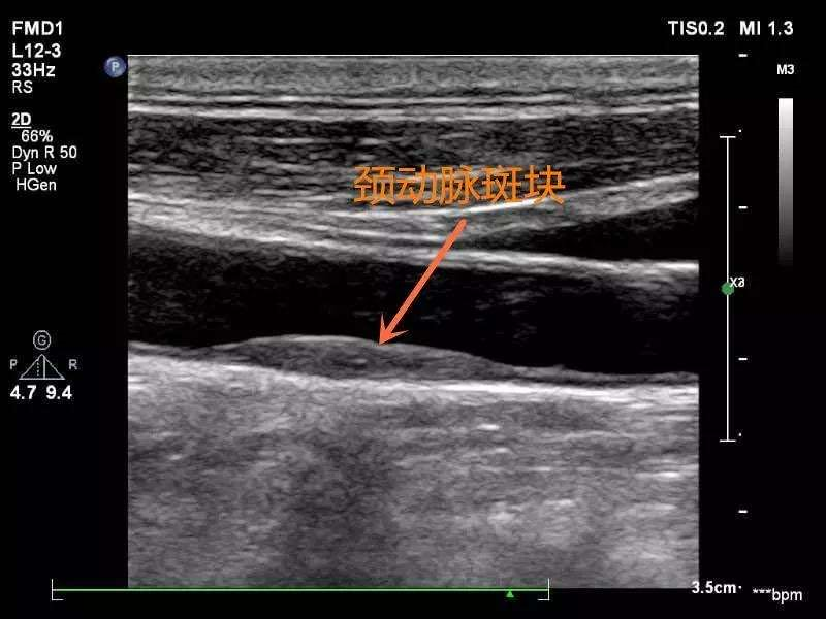

怎么知道身体里的血管有没有动脉粥样硬化呢?通常最简单而又无创的方法是做颈部动脉的超声检查,因为颈动脉就在颈部的体表,超声可以很清楚地看到颈动脉及其分支处。如果颈动脉见到斑块,提示全身大大小小的动脉血管均有斑块形成。

颈动脉软斑块